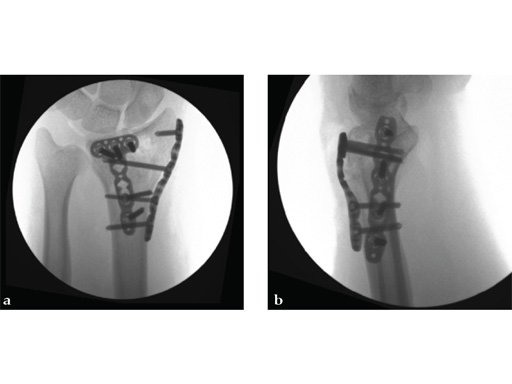

The recommended operating room technique for a dorsal shearing fracture is to apply the dorsoulnar plate first, fixed only by a cortex screw in the oblong combination hole. After, the dorsoradial plate is applied in the same way. The locking screws are then inserted in the dorsoulnar plate, starting with the most proximal hole. Finally, locking screws are placed in the dorsoradial plate in the same order. The VA instrumentation allows repositioning of nonoptimally placed screws.

Case 1: A 62-year-old man fell on his outstretched left hand while playing tennis, sustaining an intraarticular fracture of the distal radius, Mller AO Classification 23-C3.2.

Case provided by Renato Fricker, Bruderholz, Switzerland

Case 2: A 44-year-old man sustained polytrauma following a car accident. Among his injuries was a distal radial fracture, Mller AO Classification 23-C1.

Case provided by Vitezslav Ruber, Brno, Czech Republic